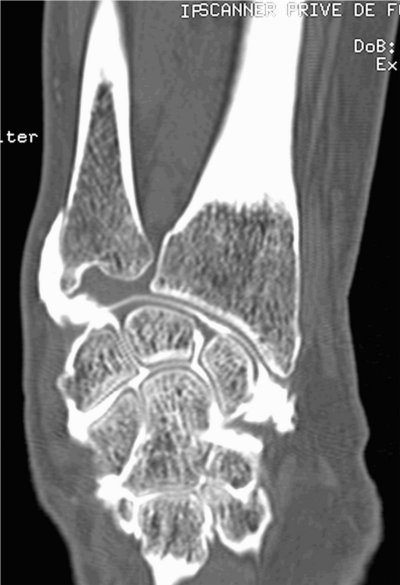

Cheville